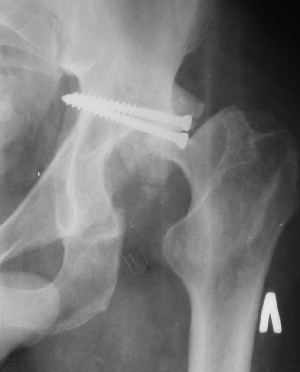

При поступлении в госпиталь 3.06.03

Больной 18 мая 2003 года в автоаварии получил перелом левой вертлужной впадины, вывих бедра. Госпитализирован в один из стационаров области.Вывих вправлен. В последствии бедро вывихивалось еще дважды. На консультацию был представлен снимок от 19.05.03г., больной переведен к нам 3.06.03г. Снимок при поступлении - перелом впадины, задне-верхний вывих бедра. 05.06.2003 г. выполнено открытое вправление вывиха левого бедра и остеосинтез стенки вертлужной впадины двумя винтами. Послеоперационный период без осложнений. Объем движений в левом тазобедренном суставе восстановился полностью. Выписан на амбулаторное лечение в удовлетворительном состоянии с рекомендациями 3 месяца ходить на костылях без нагрузки на оперированную конечность. На контрольных рентгенограммах левого тазобедренного сустава 13.10.2003 г. - признаки консолидации перелома; плотность, форма головки и состояние суставных поверхностей удовлетворительные. Разрешена дозированная осевая нагрузка, на конечность с использованием дополнительной опоры. 19.12.2003 г. больной обратился с жалобами на боли в левом тазобедренном суставе. На рентгенограммах левого тазобедренного сустава 19.12.2003 г., 20.02.04г. - асептичекий некроз головки бедра. 5.04.04г. - эндопротез. Сейчас ходит без трости, не хромает. Особенность эндопротезирования - при удалении винтов прослежена линия перелома заднего края впадины и предложено установить чашку несколько меньшего диаметра, чтобы она была покрыта несломанной частью.